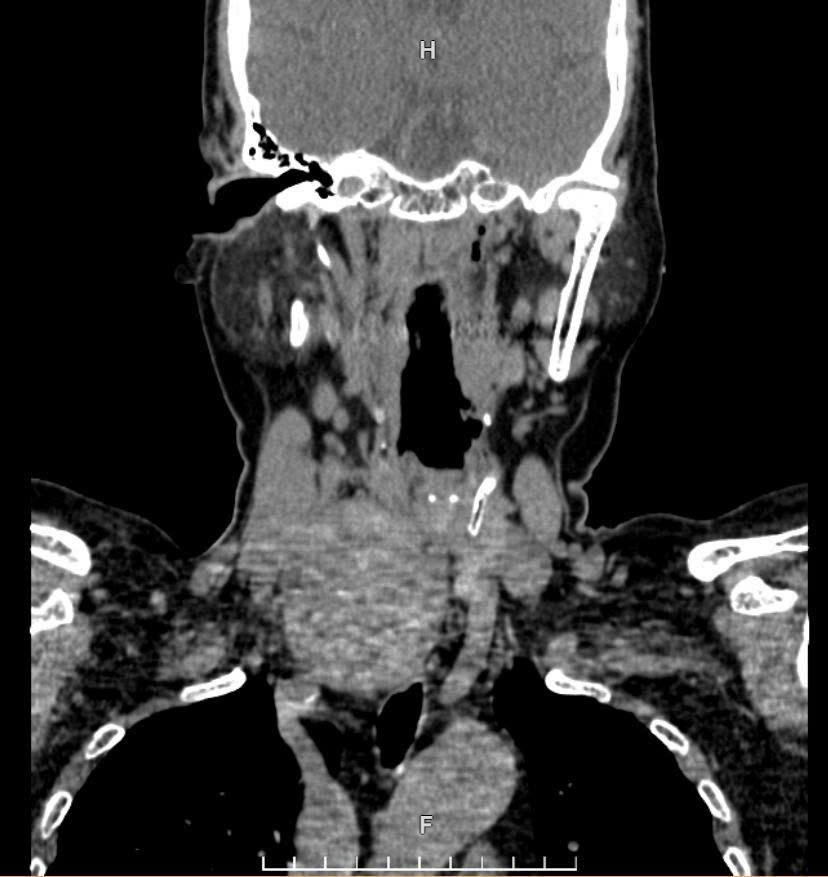

Khối u chèn ép khí quản và thực quản |

Sau khi được chuyển từ Bệnh viện Tim Hà Nội, các bác sĩ Bệnh viện Ung Bướu Hà Nội xác định bệnh nhân có khối u thùy phải tuyến giáp kích thước 6x8cm, nằm kẹt giữa thực quản và khí quản. Khối u này đã chèn ép khí quản đến mức đường thở chỉ còn khoảng 2mm trên đoạn dài 20mm, gây biến dạng giải phẫu nghiêm trọng. Khí quản của bệnh nhân còn bị đẩy lệch trái 2cm, xẹp và dễ co thắt, khiến việc tiếp cận phẫu thuật vô cùng khó khăn. Đặc biệt, khối u tăng sinh mạch rất mạnh, tiềm ẩn nguy cơ chảy máu cao trong và sau mổ.